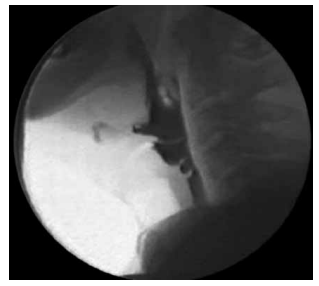

Analise a figura a seguir, que apresenta um exame de

imagem realizado para avaliação da deglutição:

Assinale a alternativa que apresenta corretamente o exame e a respectiva interpretação.